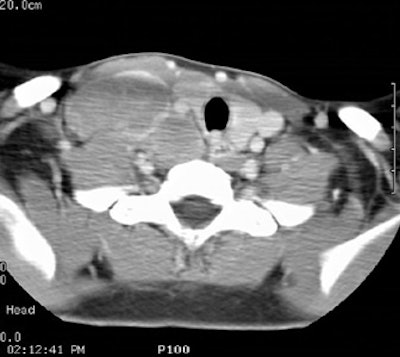

Computed Tomography: CT can detect intrathoracic sites of disease not detected on CXR in up to 20% of patients. The effect on patient management is quite variable (between 10-60% of patients), and is related to the specific protocol for which the patient is being considered. On CT there is usually an asymmetric, anterior mediastinal soft tissue mass which may invade the chest wall. Bulky mediastinal nodal disease can be associated with interstitial edema due to lymphatic/venous obstruction. Although typically homogeneous, larger masses may contain areas of decreased attenuation representing necrosis or cyst formation. Calcification is RARE prior to therapy. A pleural effusion is seen in up to 30% of cases and is usually felt to be related to lymphatic/venous obstruction from the mediastinal mass [ACR Syllabi #40:p.134 suggests effusions are found in only 2% of cases]. Benign pericardial effusions may also be seen in such patients.